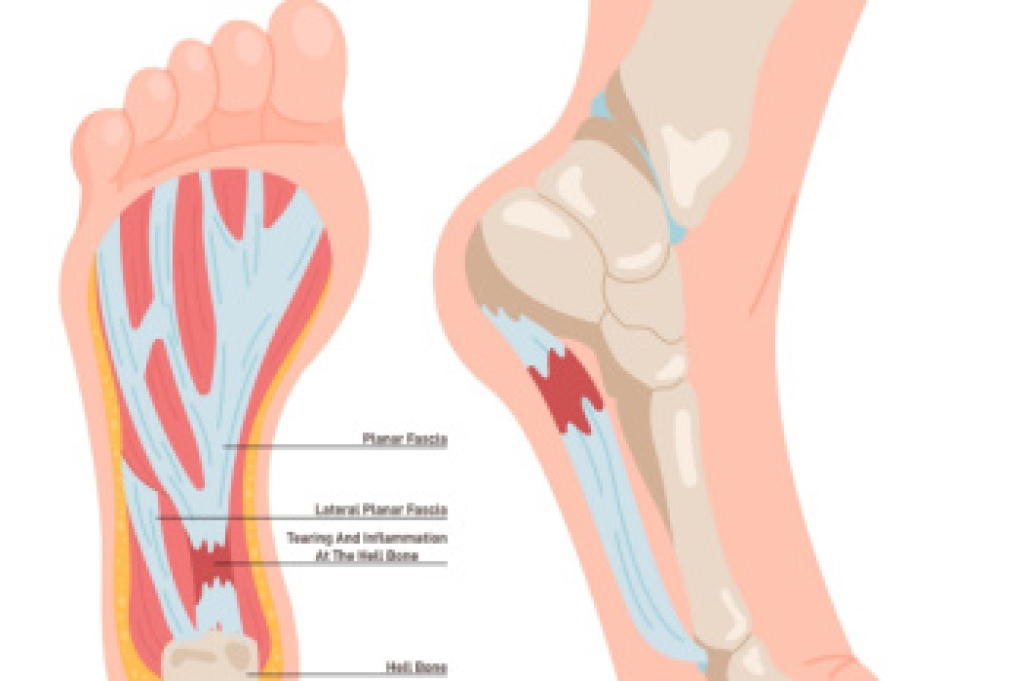

- Plantar Fasciitis

- Bone Spurs